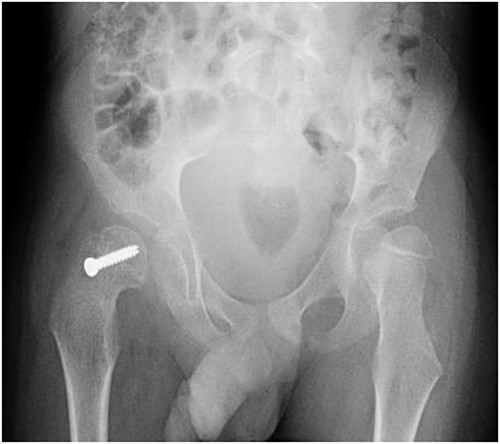

A 5-year-old independent ambulatory Middle Eastern boy with CP who was born preterm and developed grade III intraventricular haemorrhage and periventricular leucomalacia and was on AEDs, including valproic acid (VPA) and levetiracetam (LEV), for >3 years and was controlled over the last year (no history of seizure attack) presented to the emergency room (ER) with right hip pain and inability to bear weight for 4 weeks; the patient had no history of fever or trauma. Physical examination shows a thin, the weight is 12 kg, the height is 101 cm, vital signs within the normal range, tenderness over the right hip, and external rotation of the right hip, with restricted hip mobility. A radiological study was performed ~3 months before the patient presented to the ER for follow-up examination of a left hip coxa valgus deformity with no apparent abnormalities in the right hip (Fig. 1). Initial imaging studies conducted in the ER showed an anterior–posterior view of the pelvic radiograph, revealing Klein’s line [13] not intersecting the capital femoral epiphysis (Fig. 2), and frog-leg lateral view radiograph of the right hip (Fig. 3) confirmed SCFE and Southwick’s slip angle [13] of ~50° (moderate). Laboratory findings were clear for endocrine and renal diseases or infection, except for low vitamin D (total 25-OH Vitamin D: 43.4 nmol/L), suggesting vitamin D insufficiency. The diagnosis was confirmed with clinical and radiological studies as right-sided unstable SCFE requiring surgery. Surgical intervention was performed with percutaneous in situ fixation using a single fully threaded 4.5-mm cannulated screw (Fig. 4). Postsurgical rehabilitation included non-weight-bearing right lower extremities for 6 weeks. Regular follow-up with serial radiology studies showed stable fixation with no migration of screw or further slippage at 6 weeks (Fig. 5) and 3 (Fig. 6), 15 (Fig. 7), and 36 months (Fig. 8). During follow-up, a painless range of motion in the right hip was observed, with full weight-bearing and resumption of his usual activities with no complaints.

Pelvic anterior–posterior radiograph showing SCFE in the right hip, with Klein’s line not intersecting the capital femoral epiphysis